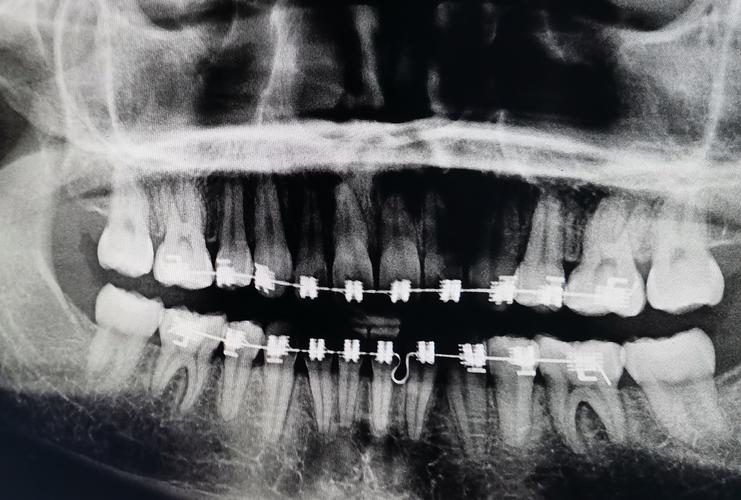

深圳美奥口腔正畸的核心竞争力在于“数字化精准矫正体系”,从初诊到矫正结束,全程依托3D数字化口扫、CBCT影像分析、计算机辅助设计(CAD)等先进技术,实现牙齿移动的精准预测与方案可视化,通过口扫设备可在5分钟内获取患者口腔内的三维数据,避免传统取模的恶心不适;结合AI算法模拟牙齿排齐过程,医生可提前预判矫正效果,并与患者共同调整方案,确保“功能与美学双重达标”。

- 初诊检查:包括口腔检查、CBCT拍摄、头影测量分析、取模(或口扫),全面评估牙齿、颌骨、面部肌肉等情况,判断是否需要拔牙、扩弓等辅助治疗。

案例1:青少年骨性龅牙矫正

患者:小明,14岁,主诉“牙齿前突,不敢笑”,检查显示为轻度骨性龅牙(上颌前突,下颌后缩),伴有牙列拥挤,治疗方案:拔除4颗第一前磨牙,采用自锁托槽矫正,结合微种植体支抗内收上前牙,同时使用颌板引导下颌发育,矫正周期:2年3个月,效果:牙齿排列整齐,侧面轮廓改善明显,嘴唇自然闭合,面部协调度提升。 -